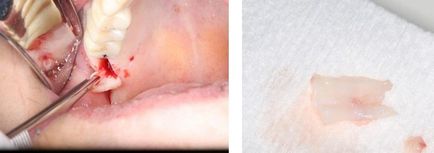

Un bisturiu microchirurgical este utilizat pentru a crea o cutie de grefare.

Se efectuează gardul și de-epitelizarea ulterioară a grefei gingivale de la nivelul maxilarului superior.

Un bisturiu microchirurgical este utilizat pentru a crea o cutie de grefare.

Se efectuează gardul și de-epitelizarea ulterioară a grefei gingivale de la nivelul maxilarului superior.